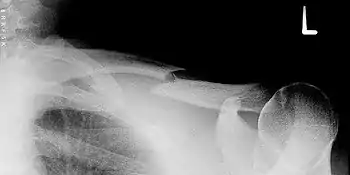

Fracture de la clavicule

Cette fracture est extrêmement fréquente et intéresse environ 5 % des entrants aux urgences hospitalières. Elle a lieu le plus souvent au tiers moyen de la diaphyse. Elle peut survenir chez le nouveau-né à la suite d'un accouchement difficile (fracture obstétricale).